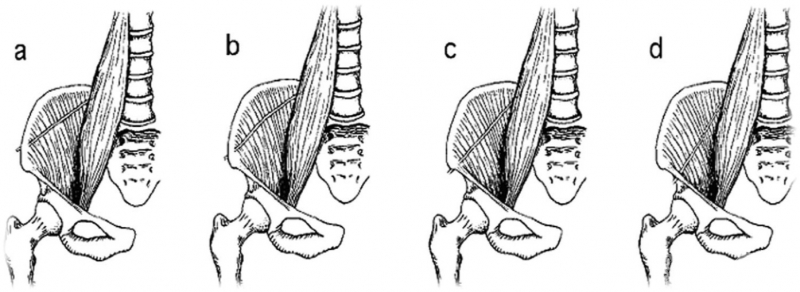

有学者将股外侧皮神经穿出点的解剖变异进行归纳,将其分为以下四型:

A型:髂前上棘后2cm以远通过髂嵴(2.5%);

B型:髂前上棘后2 cm内通过髂嵴(10.0%);

C型:经髂前上棘通过(32.5%);

D型:经髂前上棘前(内)侧、腹股沟韧带外1/3深面通过髂筋膜与腹股沟韧带(或韧带外侧端两层)之间的骨纤维管道出骨盆入股部(55.0%)。

从分型中我们可以看出,D型为大部分股外侧皮神经穿出点所在部位,因此髂前上棘前内侧局部为常见的股外侧皮神经穿出点。